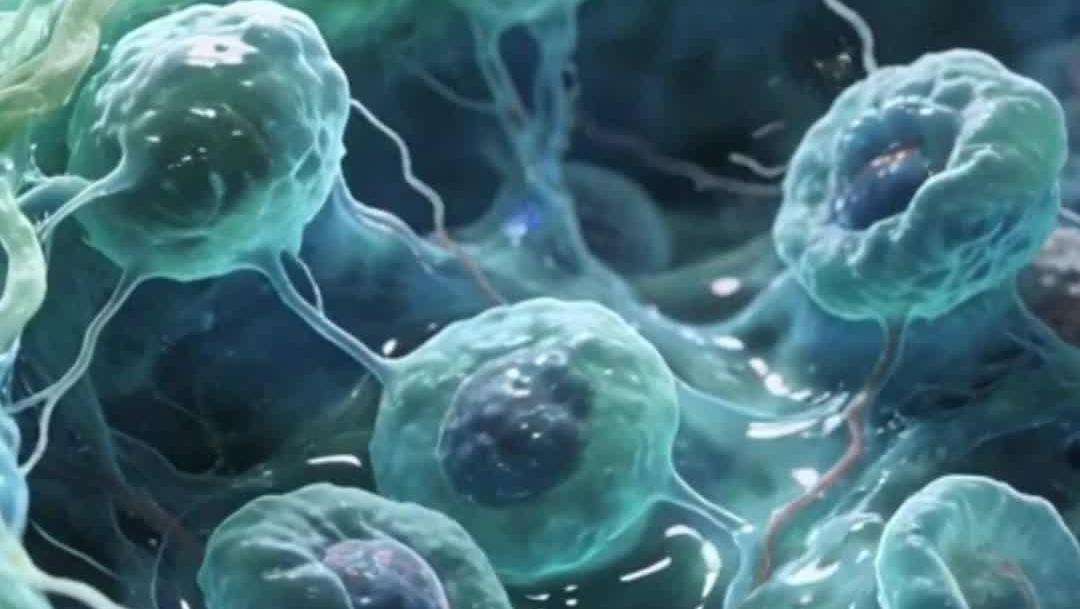

科學(xué)家用人類干細(xì)胞構(gòu)建出“類血細(xì)胞”

人類皮膚細(xì)胞育成功能性卵子

干細(xì)胞移植逆轉(zhuǎn)動(dòng)物中風(fēng)損傷